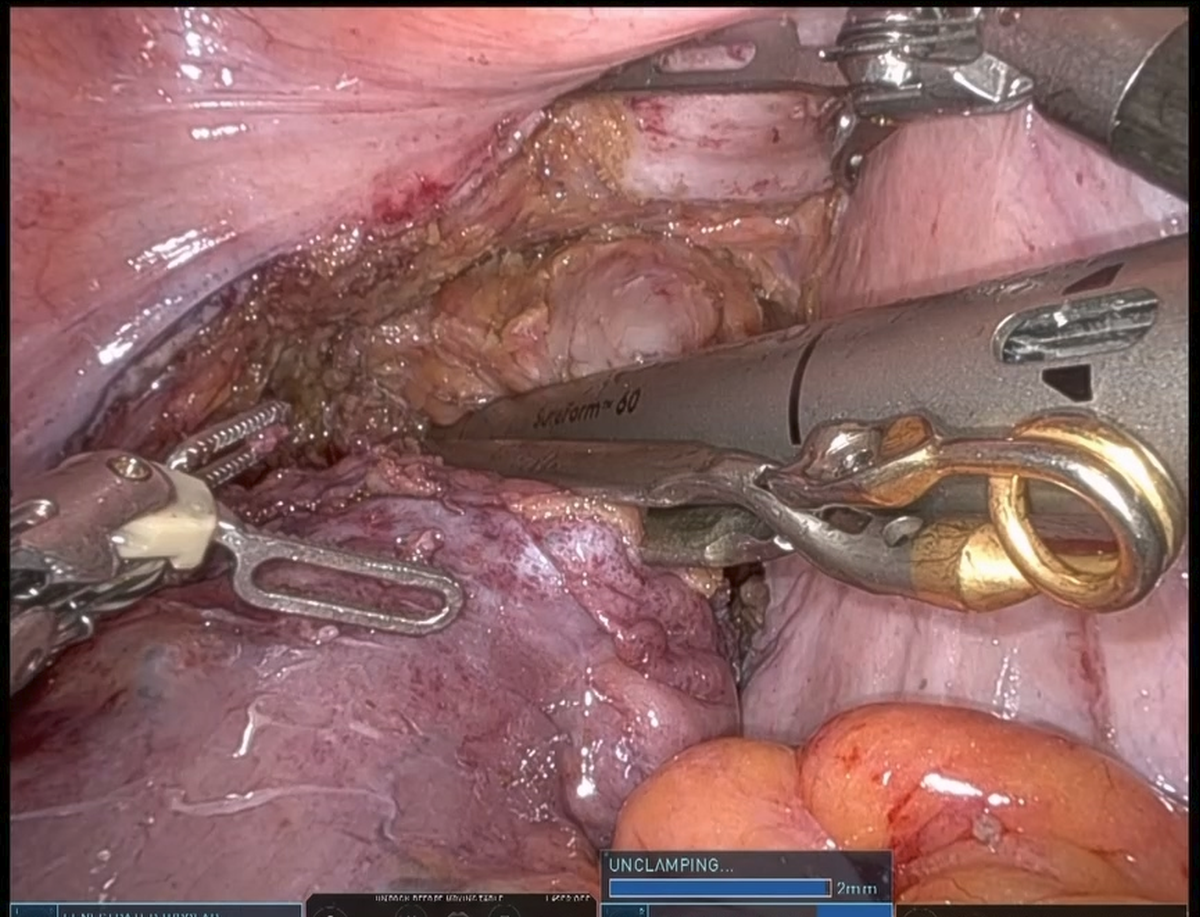

ロボット支援下手術は、腹腔鏡手術の一種として、2018年に直腸癌、2022年に結腸癌が保険収載となりました。ロボットが勝手に手術を行うわけではなく、先の腹腔鏡手術と同じように体に開けたいくつかの小さな穴から内視鏡やメス、鉗子を入れ、それらを術者が操作して手術を行います。サージョンコンソールとよばれる操縦席に術者が座り、立体画像を見ながら手元のコントローラーを操作します。

患者さんのそばにあるペイシェントカートのロボットアームにその動きが伝わり、手術を行います。鉗子を機械で制御するため、腹腔鏡手術に比べて手ぶれがほとんど無く、精緻な手術を行う事が可能です。さらに、ロボット用鉗子には関節がついており、腹腔鏡手術よりも自由度の高い手術を行うことが可能です。特に、骨盤腔のような狭い場所では効果的であり、大腸癌ガイドラインでは直腸癌に対してロボット支援下手術を行うことが強く推奨されています。

当院には2025年6月に手術支援ロボット・ダヴィンチXiが搬入され、同年8月にロボット支援下手術を開始しました。内視鏡外科技術認定取得者でかつロボット支援手術認定プロクター(消化器・一般外科)が主に執刀を行っており、順調に手術件数を伸ばしています。

手術室では液晶モニターに術者が見ている画像が映し出されます。当院では55インチの大型モニターを採用しており、助手の医師や看護師などのスタッフも同じ画像を見ながらサポートを行うため、まさにチーム一丸となって患者さんの治療を行います。